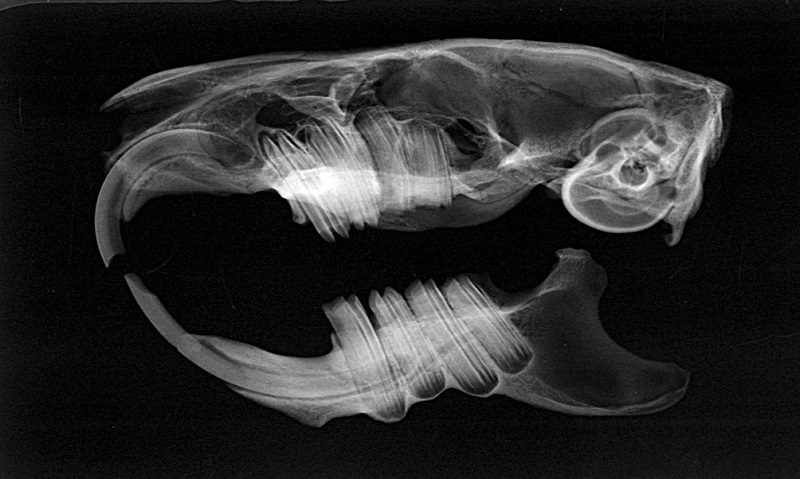

Die intraoralen Aspekte der Backenzähne lassen sich durch Inspektion mit dem Trichterotoskop oder dem Video-Endoskop nur unzureichend einsehen. Bei vollständiger Exploration der Maulhöhle in Narkose nach Einsetzen von Kiefer- und Wangenspreizern können pathologische Zahnspitzen, Zahnverbiegungen und -dislokationen diagnostiziert werden. Da aber der größte Teil des Backenzahns im Kiefer liegt, können der gesamte Zahn und seine Umgebung erst durch die Röntgendiagnostik beurteilt werden.

Eine überlagerungsfreie Darstellung aller Backenzähne ist am Schädel des Kleinsäugers nicht möglich. Daher müssen hochauflösende Röntgenbilder (Abb. [2]) bei standardisierter Lagerung in mehreren Ebenen angefertigt werden, um Zähne und Kiefer sicher beurteilen zu können. Die in diesem Artikel dargestellten CT-Bilder wurden experimentell mit einem Mikro-CT aus der Werkstoffprüfung an Knochenpräparaten angefertigt (Abb. [3]). Sie sind in ihrer Auflösung nicht mit den üblicherweise vorhandenen klinischen CT-Bildern vergleichbar. Gerade für die feinen und feinsten Veränderungen an Zähnen und Kiefern ist die klassische (Dental-)Röntgentechnik immer noch unübertroffen [[5]]. Zur isolierten Darstellung der Unterkieferäste wird eine Schrägprojektion mit einer Kippung von etwa 40° verwendet.